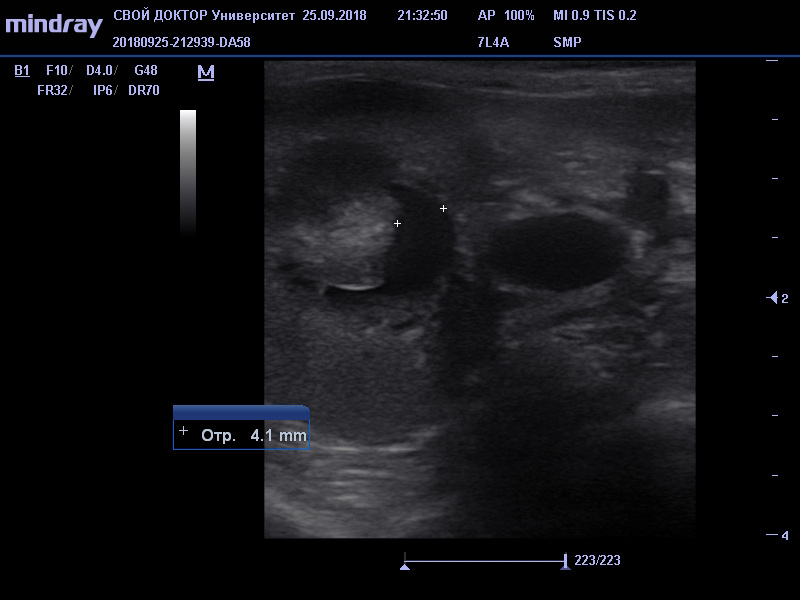

На приеме были выявлены следующие клинические признаки: нормальная температура тела, бледность слизистых оболочек, резкий запах из ротовой полости, средняя степень обезвоживания, при аускультации легких и сердца шумов не обнаружено, болезненность брюшной полости, пальпировалась увеличенная левая почка. Было выполнено УЗИ брюшной полости - обнаружилась уменьшение правой почки, и наоборот резкое увеличение левой почки с признаками нефрита. Был сделан вывод, что правая почка уже давно не выполняла свою очистительную функцию (о чем говорили ее маленькие размеры и резкое снижение кровотока), в данный же момент единственно работающая левая почка была воспалена. Были сданы общий клинический и биохимический анализы крови.